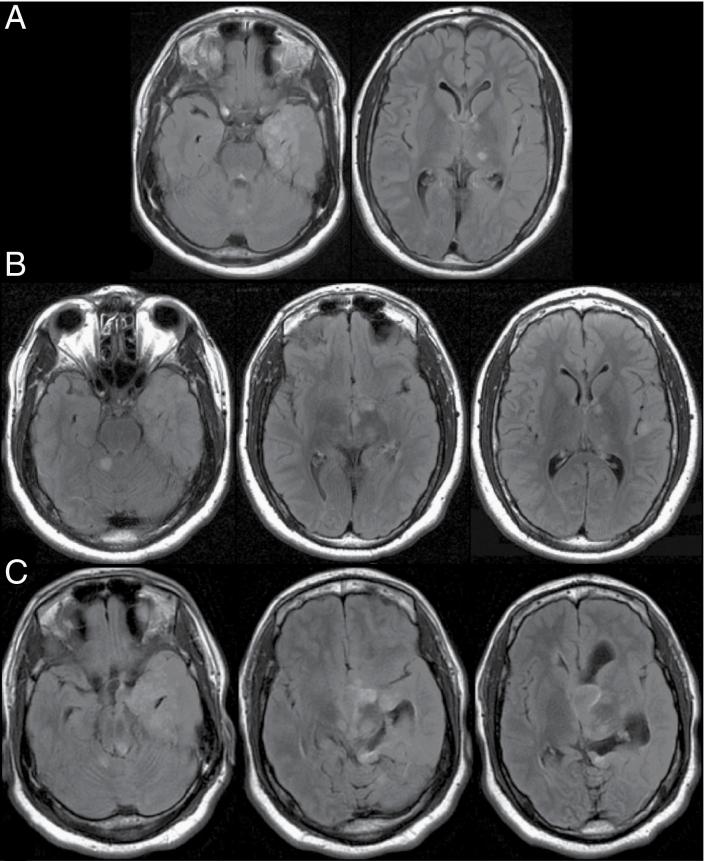

A 19-year-old man with a history of epilepsy and autism presented with acute hydrocephalus. MRI scans from 2013 to 2016 demonstrated unchanged abnormal areas of cortex in the left temporal lobe with extension into the deep gray-white matter. On presentation to our clinic in 2019, the lesion demonstrated significant progression. The patient's tumor was identified as RGNT, WHO grade I. One hundred thirty patients were identified across 80 studies.

一名有癫痫和自闭症病史的19岁男性出现急性脑积水。2013年至2016年的MRI扫描显示左颞叶皮质异常区域无变化,并延伸至深部灰白质。2019年到我们诊所就诊时,病变有显著进展。该患者的肿瘤被确诊为WHO I级RGNT。通过80项研究共确定了130例患者。